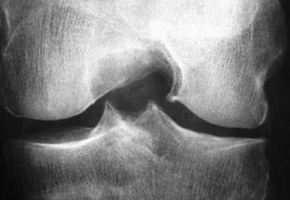

Arthrose : la prise en charge ne s’améliore pas

L’arthrose est une maladie très fréquente puisqu’elle touche 17% de la population en France (9 à 10 millions de personnes atteintes dont 6 à 7 millions symptomatiques). Son incidence augmente du fait du vieillissement de la population et de l’épidémie d’obésité de sorte que l’arthrose pourrait concerner 23% de la population en 2030. Il s’agit de la deuxième cause d'invalidité, et de la deuxième cause de consultation chez le médecin généraliste.